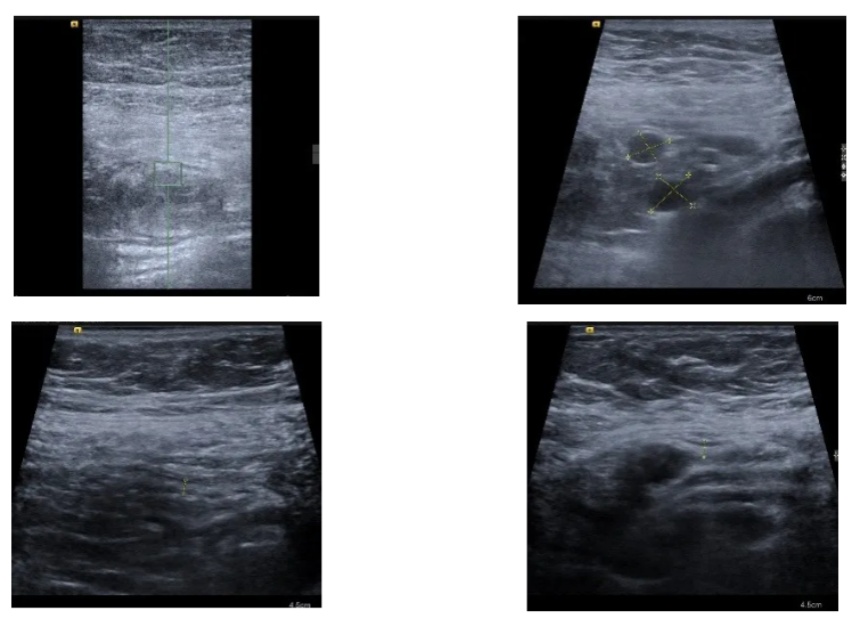

入院时患者的肠道超声报告提示:

•小肠5区肠壁增厚,Limberg I,肠系膜周围见多发肿大淋巴结;

•小肠6区肠壁增厚,Limberg I,盆腔内、小肠周围见少量积液;

•升结肠、横结肠、降结肠、乙状结肠未见明显异常。

在进行治疗、患者症状基本消失后复查了肠道超声,上述节段的小肠炎症基本在超声下都消失了,再加上患者症状也基本消失,医生们在治疗上进行了调整,逐步开放了饮食,同时进行了其他一系列的检查明确了诊断,患者也平稳出院了,近期随访下来患者没有出现症状反复,生活状态良好。